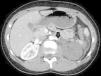

Niño de 13 años sin antecedentes médicos de interés, que acude al servicio de urgencia por traumatismo craneal y abdominal tras caída accidental de bicicleta. Se realiza TAC de cráneo en el que no se evidencian lesiones secundarias al traumatismo. En la TAC abdomino-pélvica se observan 2 focos contusivos en bazo, sin sangrado activo y ausencia de captación del medio de contraste del riñón izquierdo por stop brusco en región proximal de la arteria renal izquierda (fig. 1). Se realizan imágenes de tomografía en fases tardías, observando eliminación normal del medio de contraste por parte del riñón derecho y ausencia de captación de contraste por el riñón izquierdo (fig. 2). Se realiza el diagnóstico de disección de arteria renal izquierda con trombosis completa de la misma, y ausencia de paso de contraste arterial a riñón izquierdo, no siendo posible revascularización renal ni colocación de stent arterial.